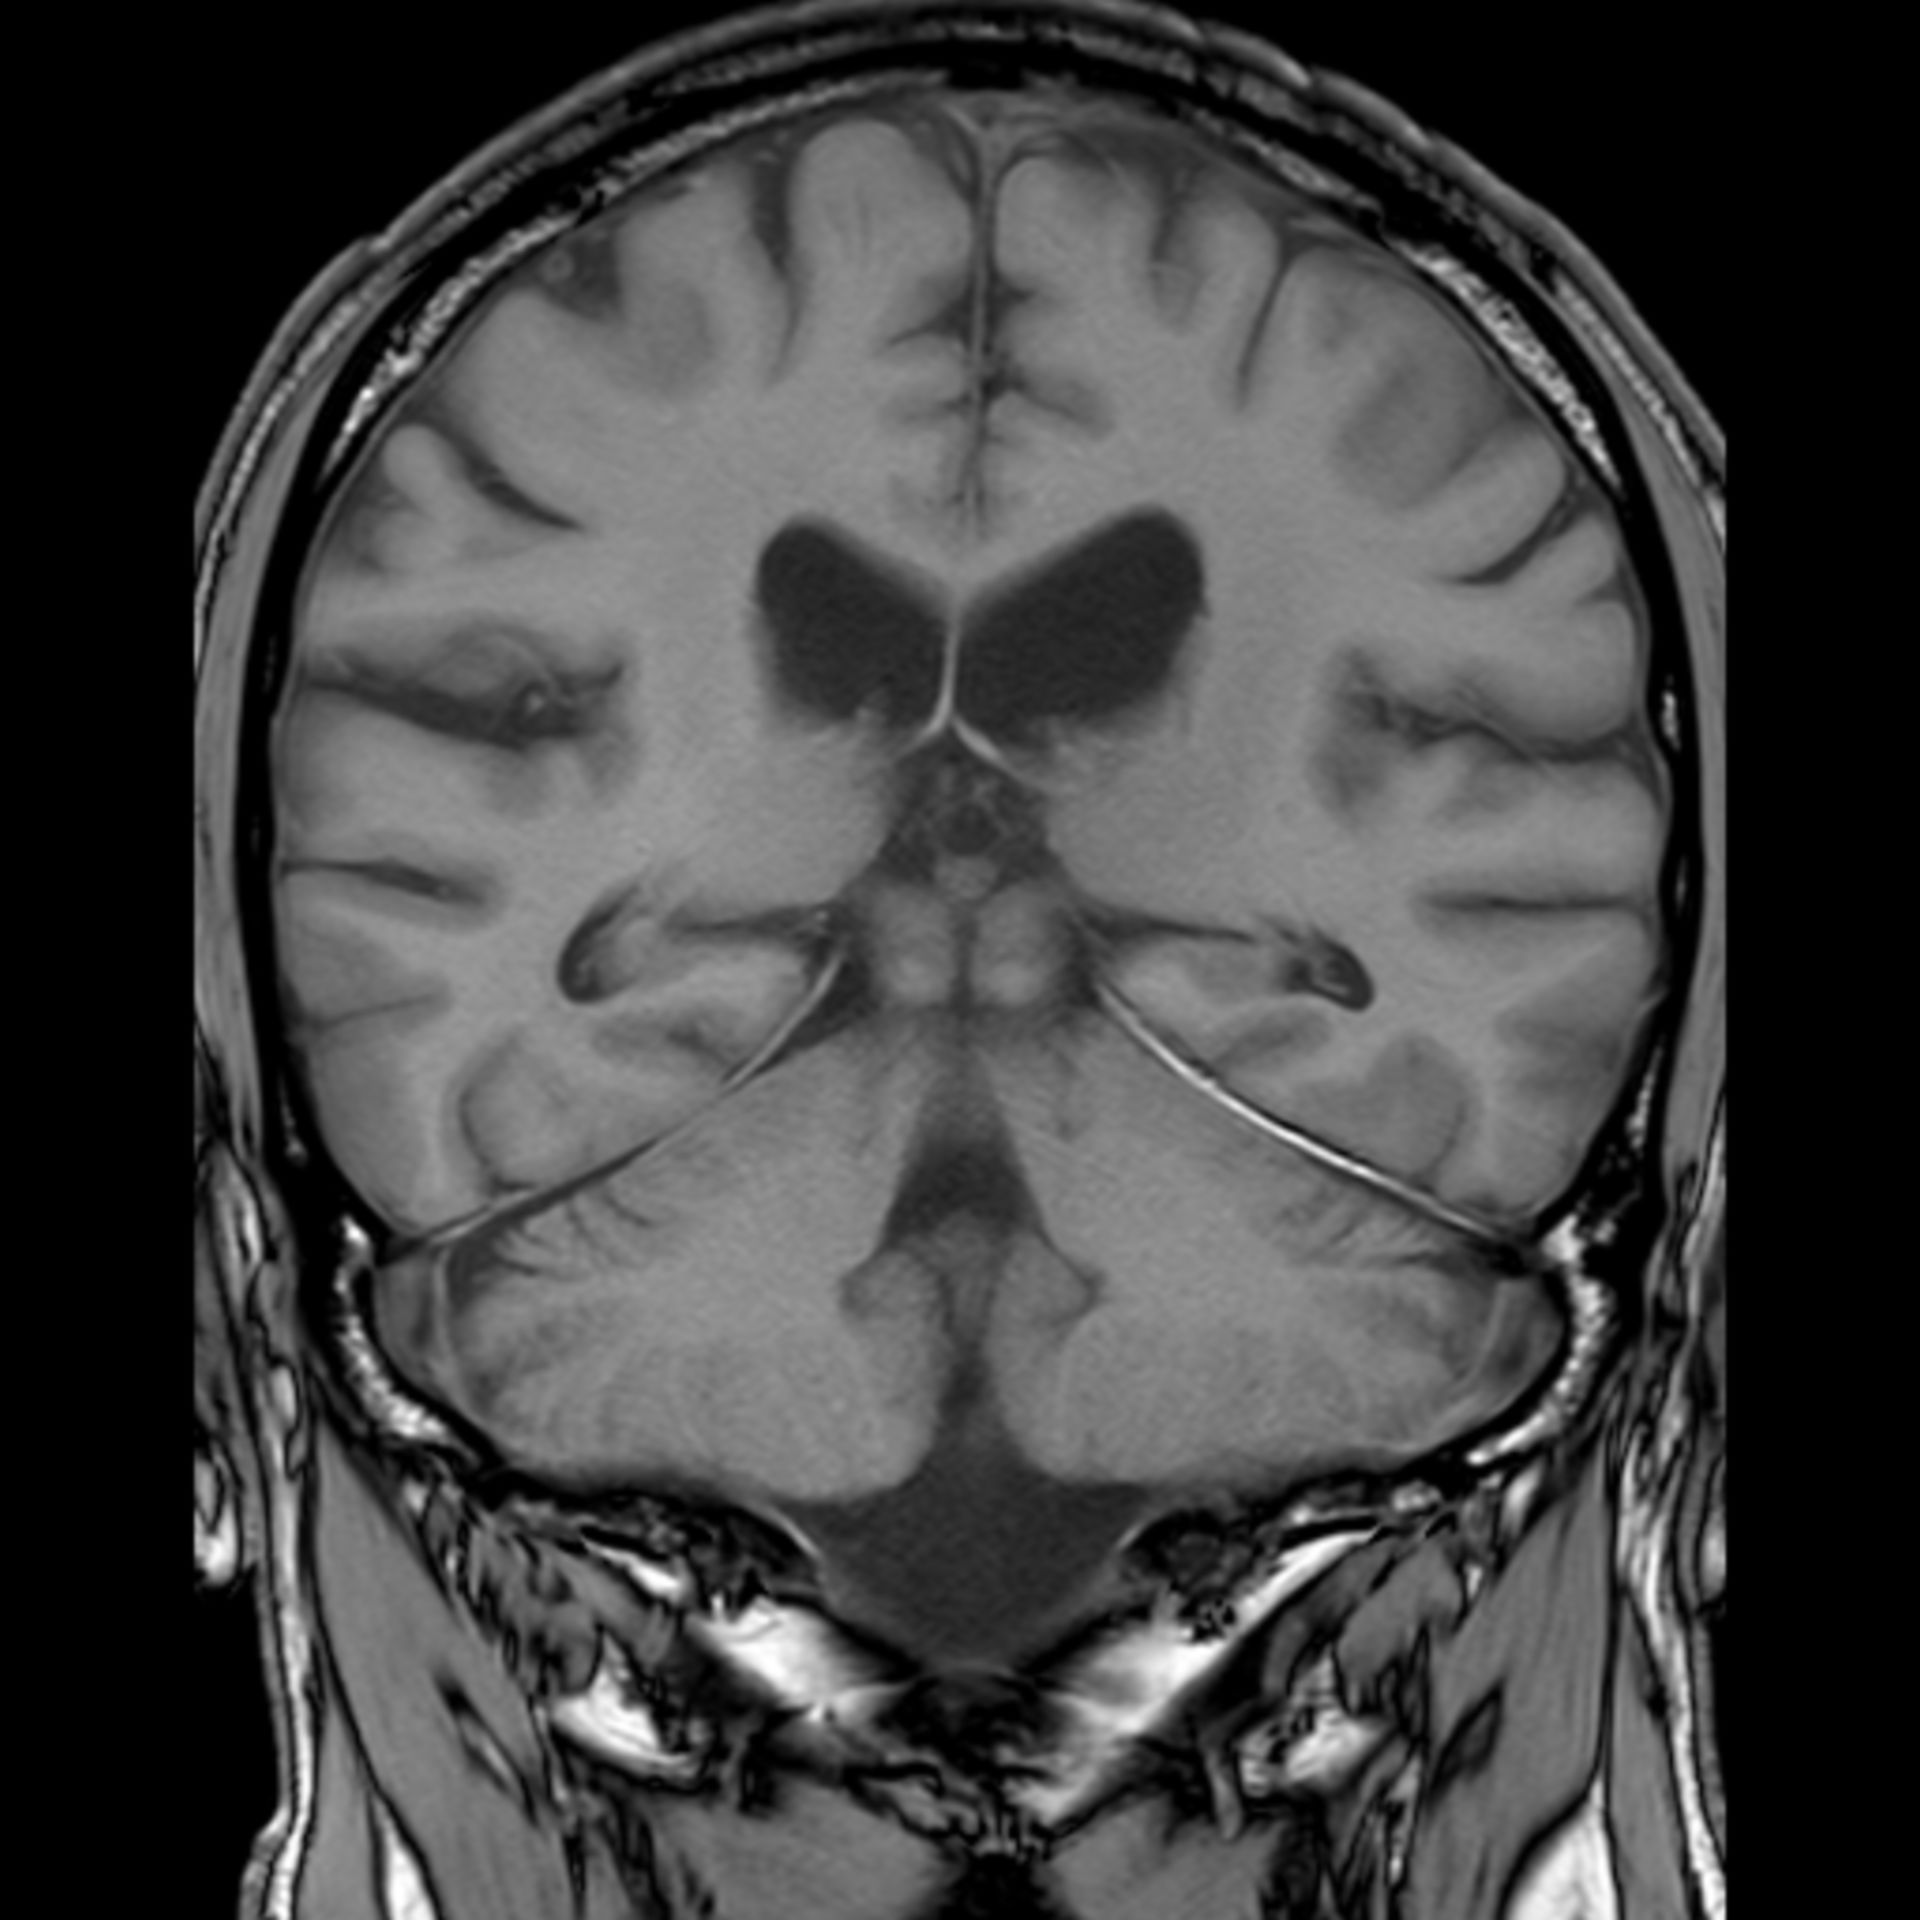

MRT Übersichtsaufnahme – DocCheck MRT Schädel – DocCheck

MRT Schädel – DocCheck MRT Bild, könnte das ein Tumor sein? Kennt sich jemand damit aus? Könnte die helle Fläche ein …

MRT Schädel – DocCheck Sichere Prostatavorsorge mittels MRT-Untersuchung der Prostata

MRT Kopf. Kleine Aufklärung? (Gesundheit, Medizin, Krankheit) Retinoblastom (MRT/T2) – DocCheck

(16/34) MRT Schädel in Sagittalebene, T₂‐gewichtet – DocCheck MRT Bilder-Hubbel-??? Hilfe (Kopf)

MRT Bilder-Hubbel-??? Hilfe (Kopf) รีวิว คอนโด Niche MONO อิสรภาพ เพียง 200 เมตร จาก MRT อิสรภาพ ใกล้ รพ.ศิริราช

MRT Schädel – DocCheck #MRT: Sungai Buloh – Kajang Line Phase 1 To Officially Start 16th December – Hype Malaysia

MRT 4 Schädel – DocCheck Taipei MRT Roadmap